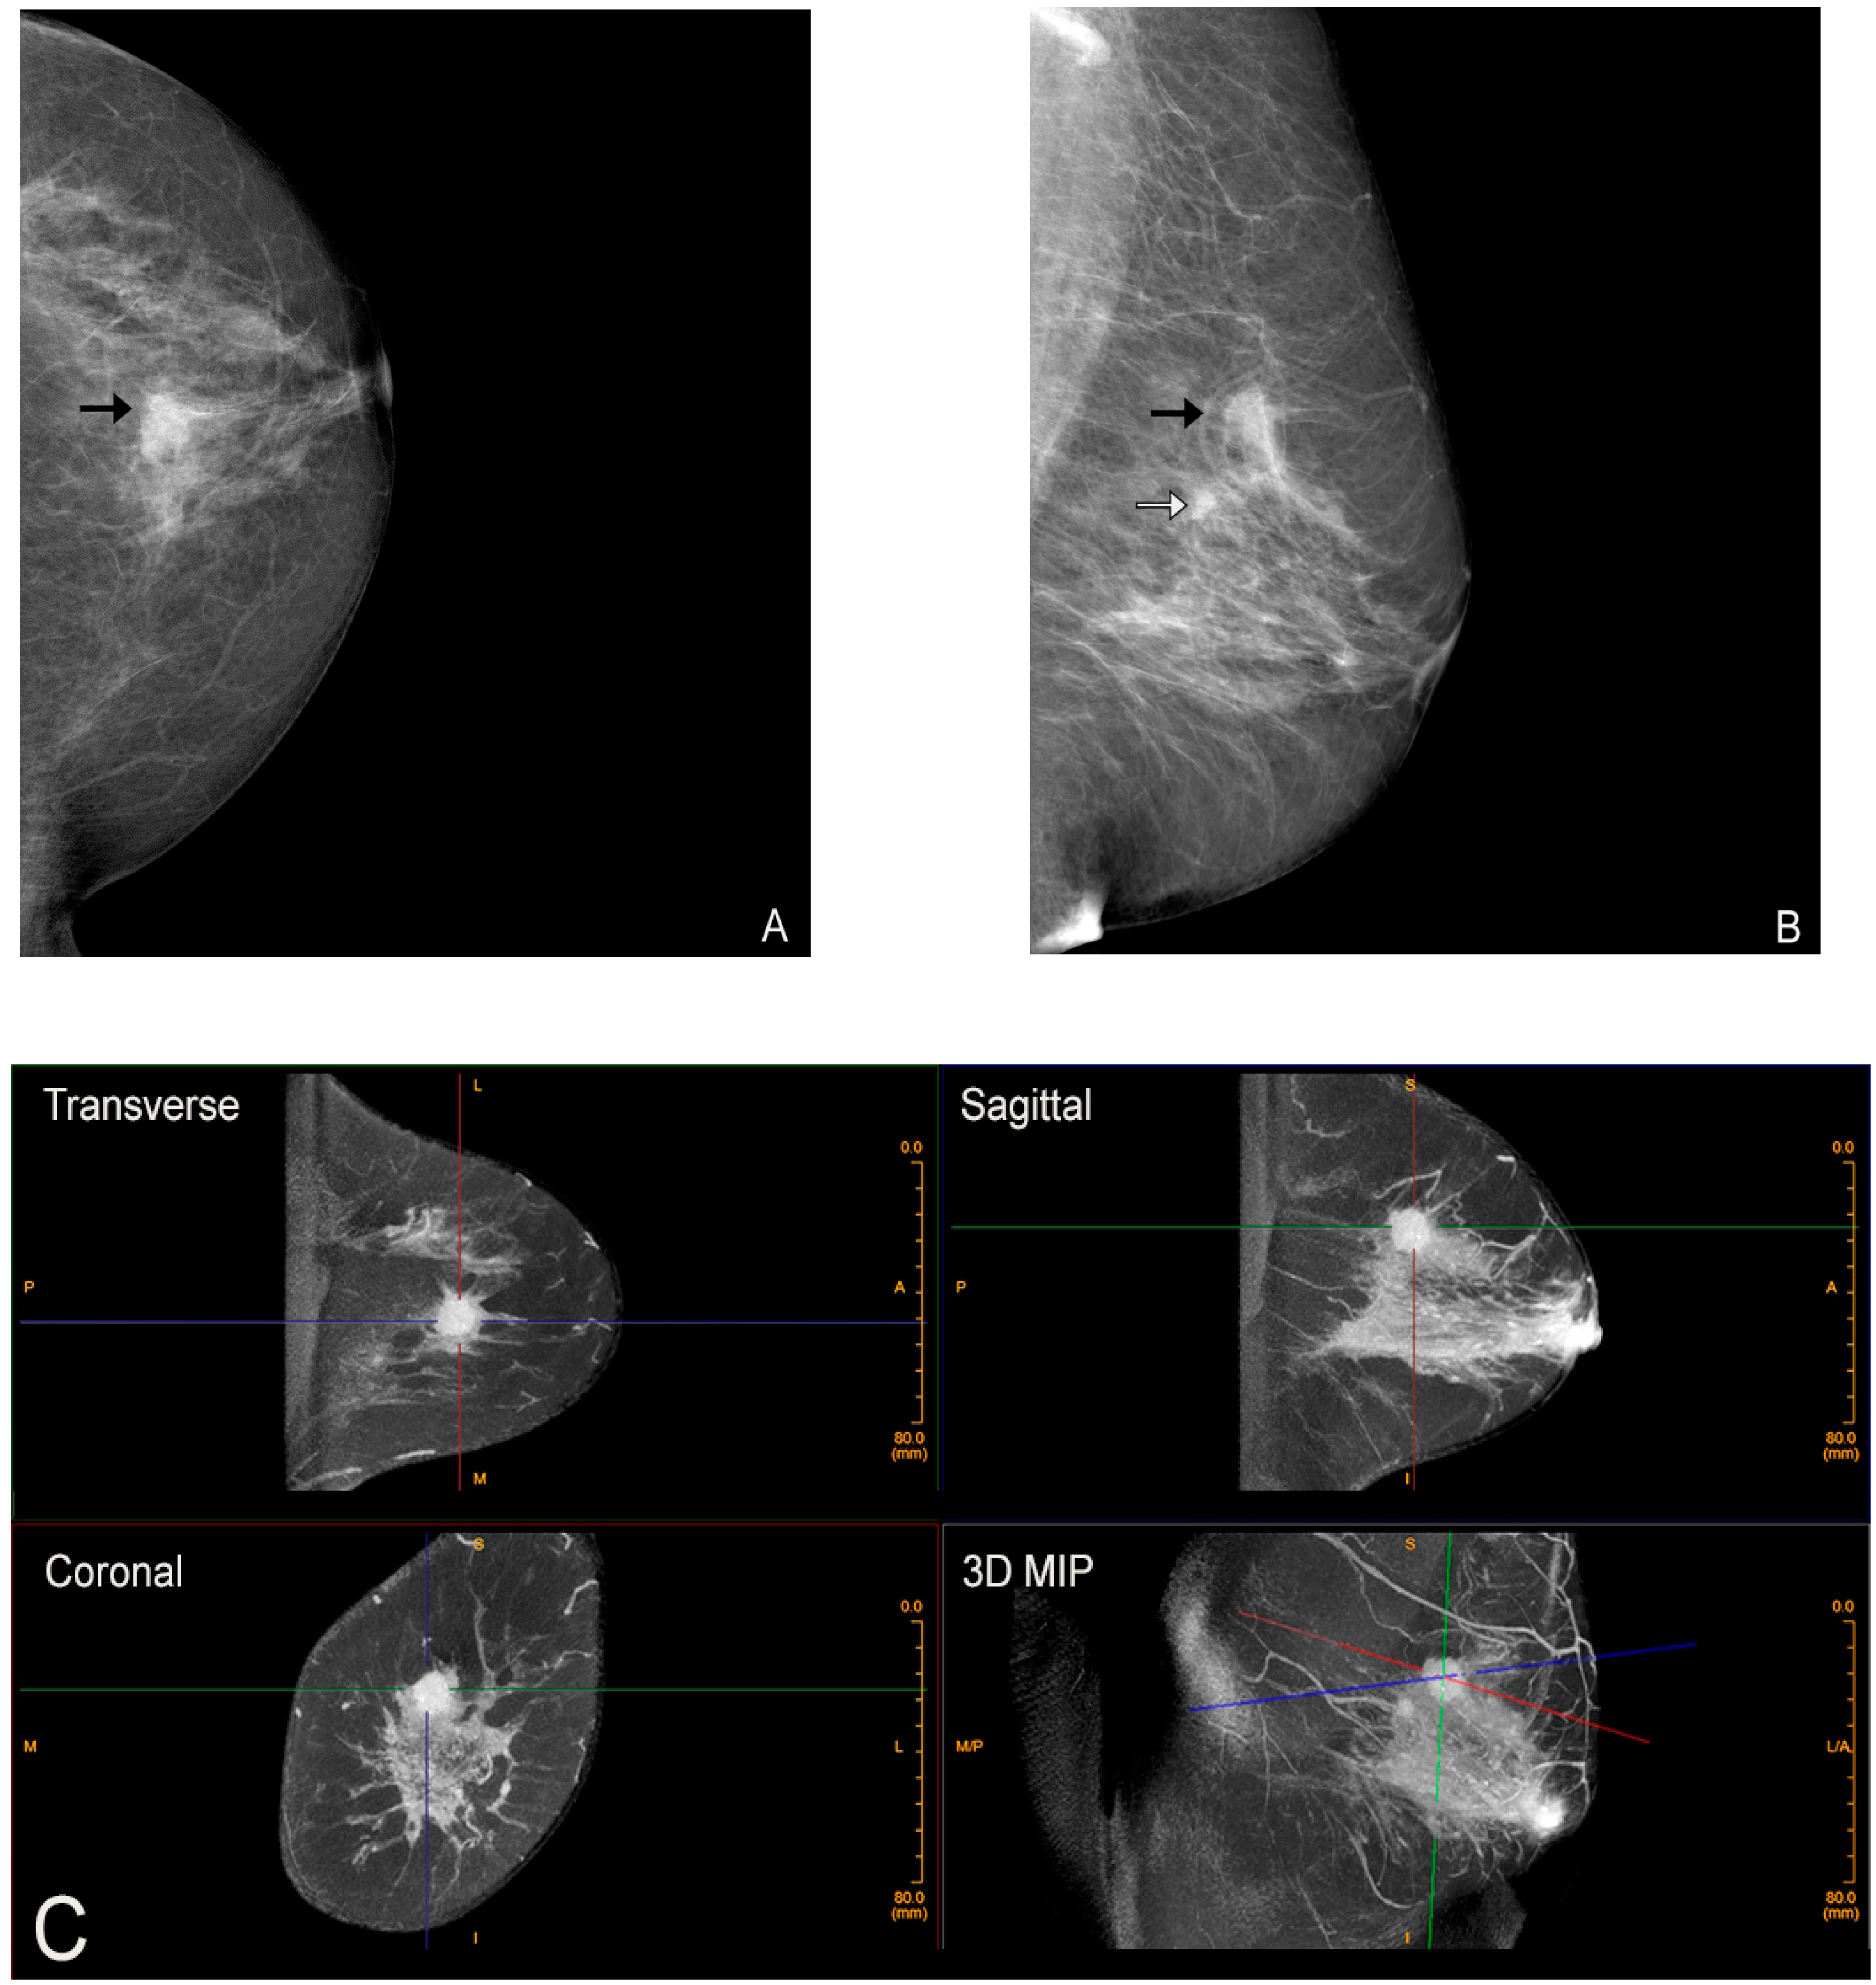

2. Cone-Beam Breast Computed Tomography